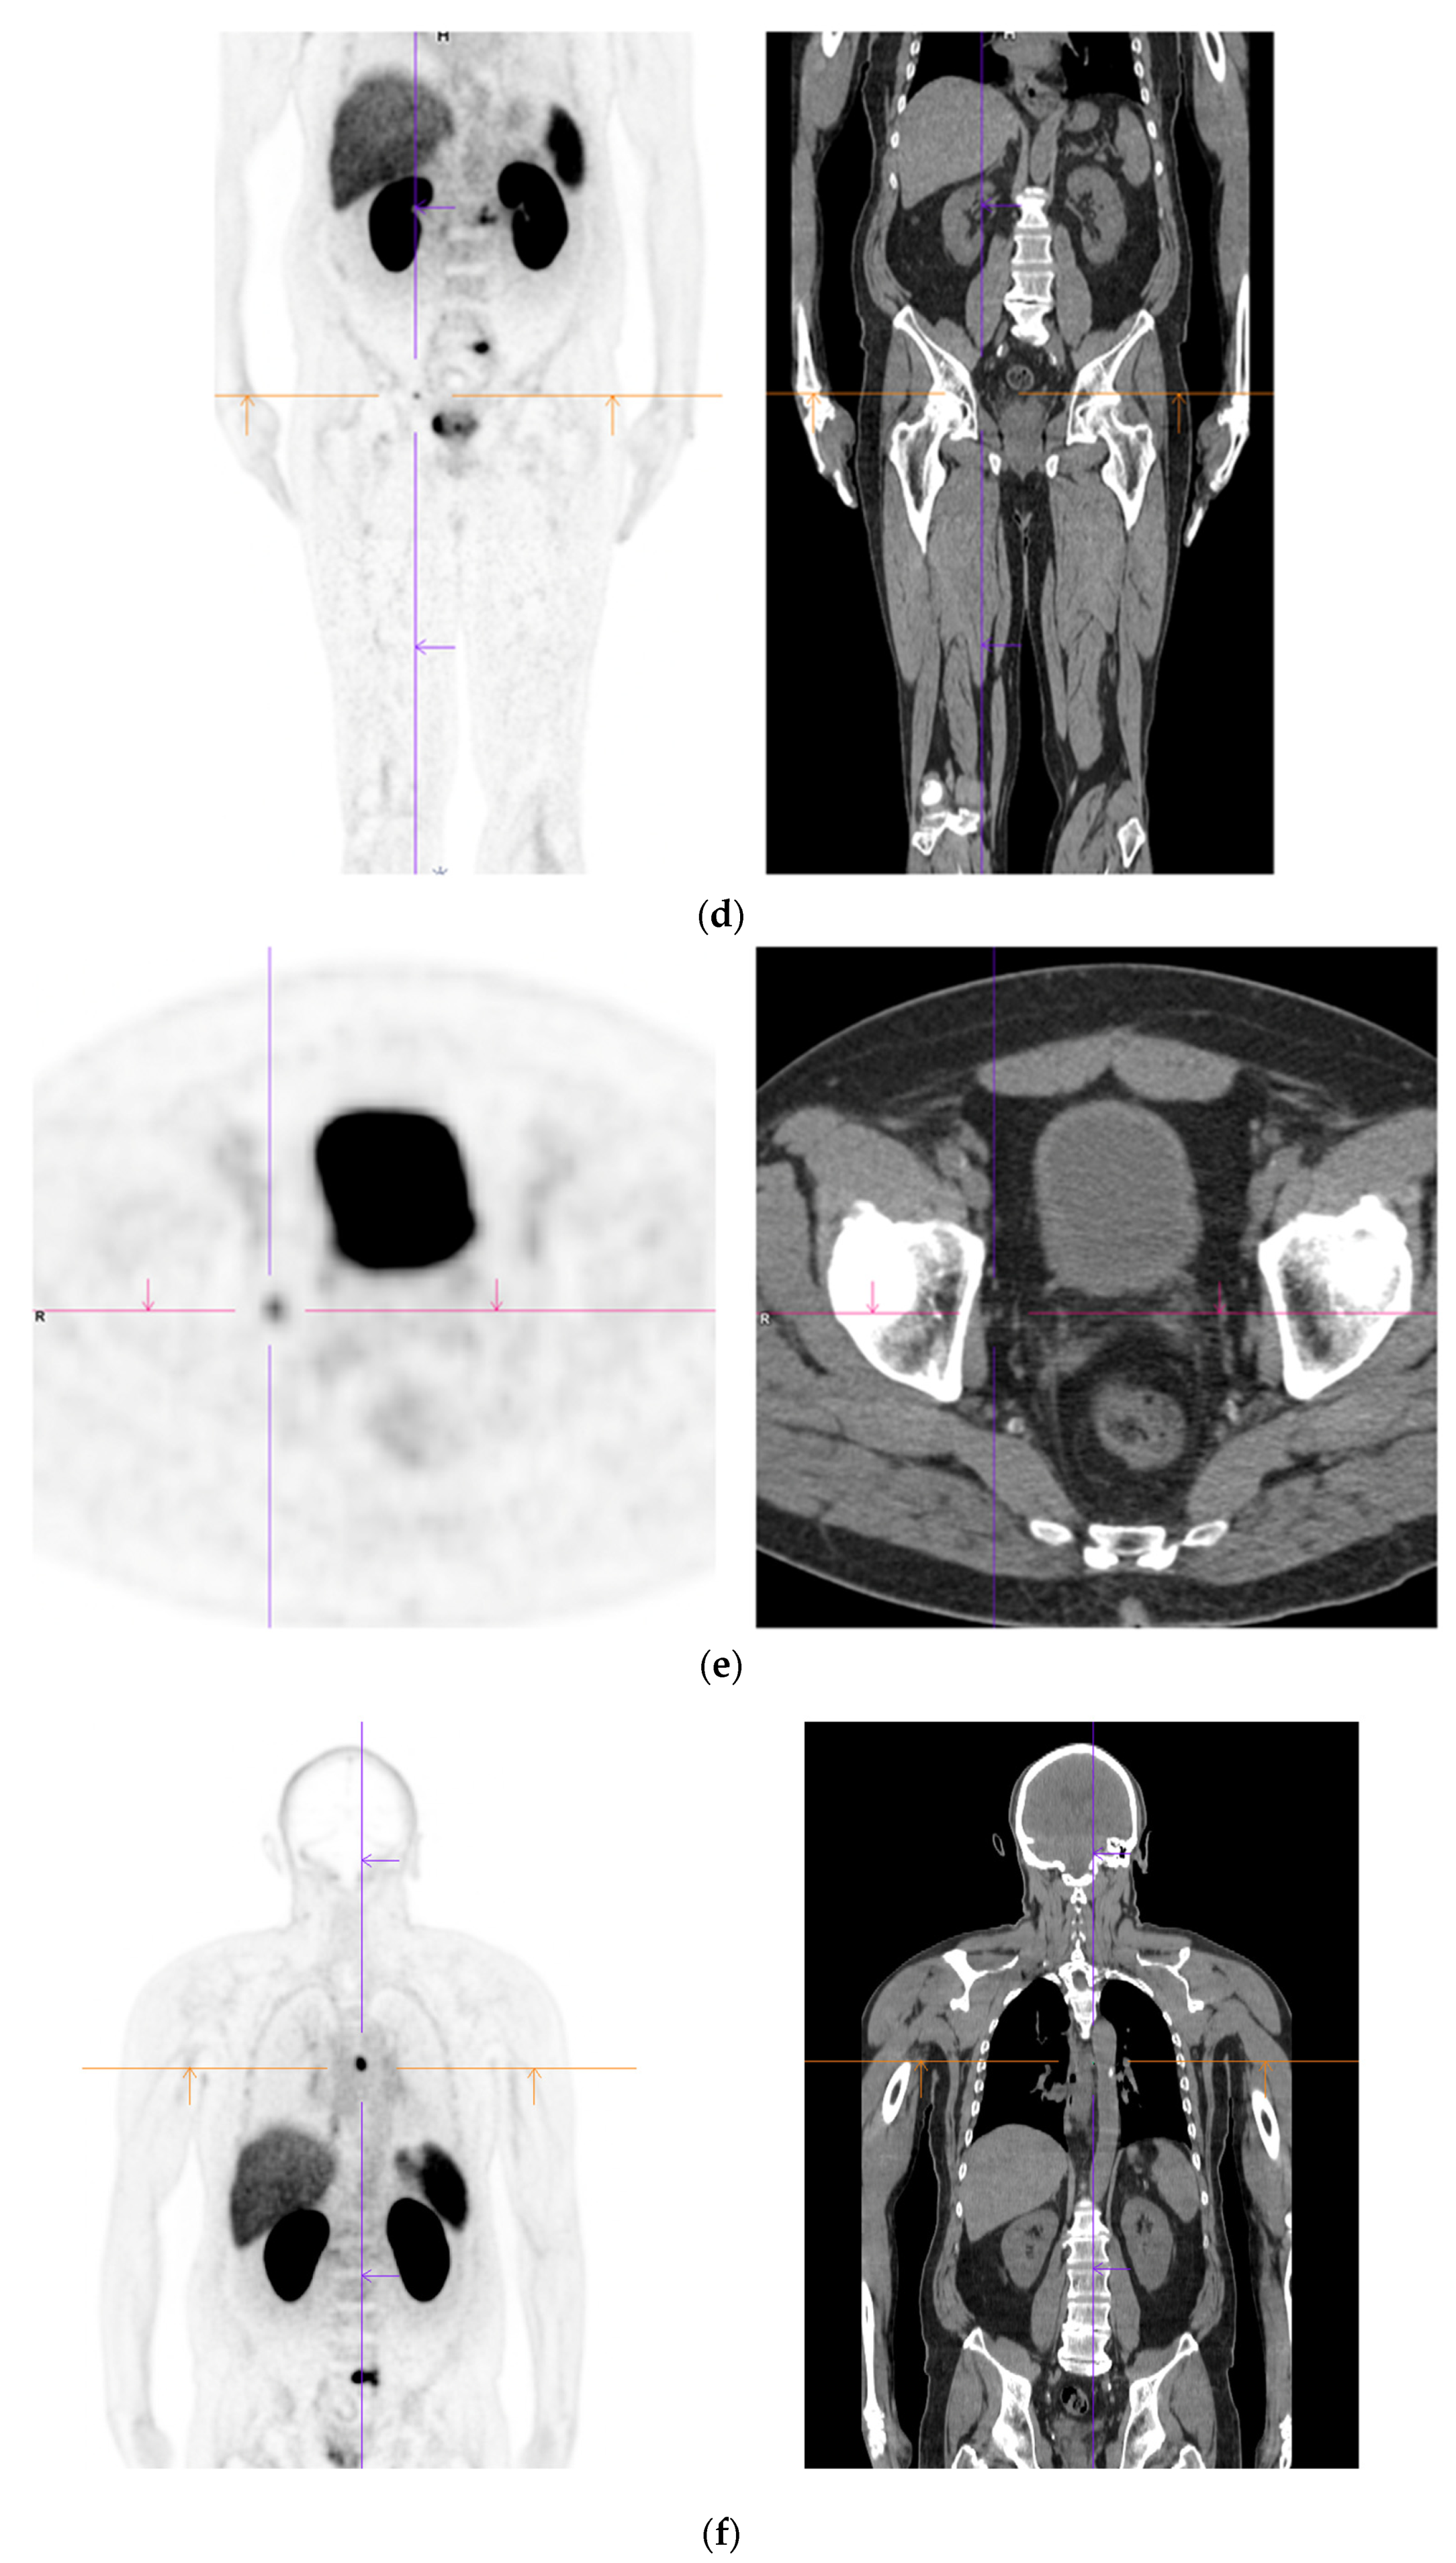

- Yaxley, J.W.; Raveenthiran, S.; Nouhaud, F.X.; Samaratunga, H.; Yaxley, W.J.; Coughlin, G.; Yaxley, A.J.; Gianduzzo, T.; Kua, B.; McEwan, L.; et al. Risk of metastatic disease on 68gallium-prostate-specific membrane antigen positron emission tomography/computed tomography scan for primary staging of 1253 men at the diagnosis of prostate cancer. BJU Int. 2019, 124, 401–407. [Google Scholar] [CrossRef] [PubMed]

- Lengana, T.; Lawal, I.O.; Boshomane, T.G.; Popoola, G.O.; Mokoala, K.M.G.; Moshokoa, E.; Maes, A.; Mokgoro, N.P.; Van de Wiele, C.; Vorster, M.; et al. 68Ga-PSMA PET/CT Replacing Bone Scan in the Initial Staging of Skeletal Metastasis in Prostate Cancer: A Fait Accompli? Clin. Genitourin. Cancer 2018, 16, 392–401. [Google Scholar] [CrossRef] [PubMed]

- Regula, N.; Kostaras, V.; Johansson, S.; Trampal, C.; Lindström, E.; Lubberink, M.; Iyer, V.; Velikyan, I.; Sörensen, J. Comparison of 68Ga-PSMA PET/CT with fluoride PET/CT for detection of bone metastatic disease in prostate cancer. Eur. J. Hybrid Imaging 2022, 6, 5. [Google Scholar] [CrossRef] [PubMed]

- Damjanovic, J.; Janssen, J.C.; Prasad, V.; Diederichs, G.; Walter, T.; Brenner, W.; Makowski, M.R. 68Ga-PSMA-PET/CT for the evaluation of liver metastases in patients with prostate cancer. Cancer Imaging 2019, 19, 37. [Google Scholar] [CrossRef]

- Damjanovic, J.; Janssen, J.C.; Furth, C.; Diederichs, G.; Walter, T.; Amthauer, H.; Makowski, M.R. 68Ga-PSMA-PET/CT for the evaluation of pulmonary metastases and opacities in patients with prostate cancer. Cancer Imaging 2018, 18, 20. [Google Scholar] [CrossRef]